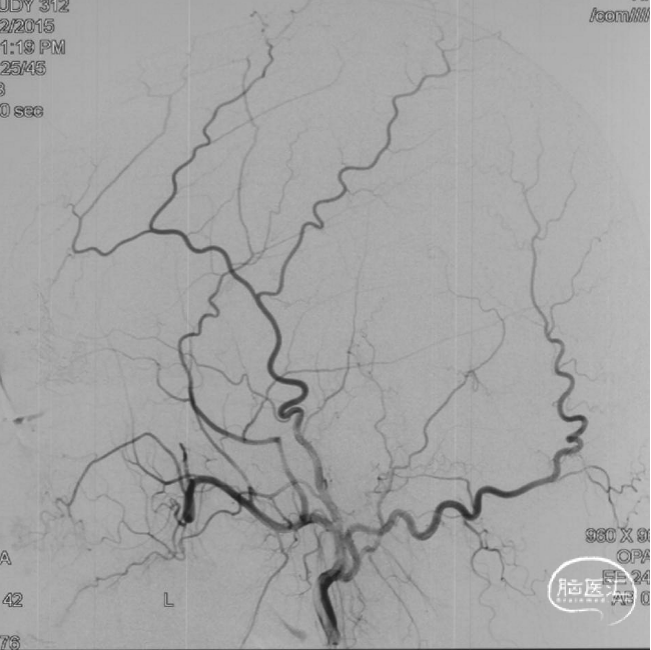

前颅窝底DAVF,由镰前动脉、双侧筛前、筛后动脉参与供血,通过皮层静脉向上矢状窦引流,引流静脉伴有瘤样扩张,Cognard IV型、Borden III型。由于脑膜中动脉-镰前动脉路径较为迂曲,超选困难,引流静脉迂曲扩张,预计到达瘘口起始端存在困难,决定经眼动脉-筛前动脉栓塞。

根据3D影像选择工作角度。

工作角度造影:黑色箭头为筛前动脉,白色箭头为筛后动脉,黄色箭头为镰前动脉,蓝色箭头为引流静脉起始部,红色箭头为视网膜中央动脉。拟通过眼动脉入路超选至筛前动脉进行栓塞。

Marathon微导管在Hybrid0.007微导丝导引下经左侧眼动脉超选至左侧筛前动脉,接近瘘口。

通过Marathon微导管超选造影,显示微导管楔入到靠近瘘口的动脉端。

通过Marathon微导管注入Onyx 18,胶向瘘口弥散,并弥散至镰前动脉。

停顿后进一步注射Onyx18,此时胶向对侧筛前动脉弥散,直至闭塞瘘口和引流静脉起始端。

最终造影瘘口完全不显影。

双侧脉络膜染色正常。

Onyx胶铸型进一步显示了瘘的结构。AFA:镰前动脉;AEA:筛前动脉;PEA:筛后动脉;DV:引流静脉。